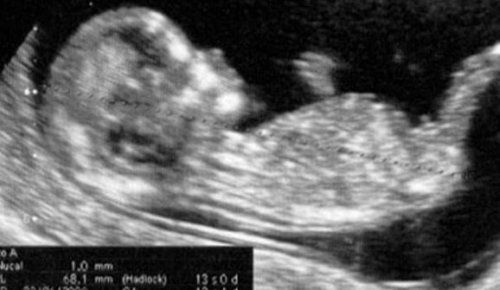

Pendant la 13ème semaine de grossesse, l’échographie de la fin du premier trimestre peut encore être réalisée si elle ne l’a pas déjà été. C’est la dernière étape de la série de contrôles auxquels nous devons faire face depuis que nous avons confirmé notre grossesse. C’est le point où l’évaluation du premier trimestre est close et on pourrait dire que la partie la plus difficile et la plus pénible (surtout si vous êtes nouvelle) est déjà passée.

A partir de maintenant, l’étape des contrôles médicaux s’arrête, mais seulement pour une courte période. Au cours de cette période, des contrôles périodiques ou mensuels sont nécessaires. Il faut s’assurer que le fœtus se développe correctement et, bien sûr, que la mère ne souffre d’aucun inconvénient.